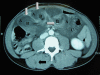

Case presentation: We report the case of a 37-year-old man who presented with multiple intussusceptions of small bowel. He required an urgent laparotomy and bowel resections. He suffered from BRBNS. This is the first reported case of multiple synchronous intussusceptions affecting both jejunum and ileum, secondary to haemangiomas occurring in an adult with BRBNS. The underlying conditions of acute abdomen in patients with BRBNS may include intramural haemorrhage, infarction, volvulus or intussusception of bowel. Treatment options include pharmacological manipulation, bowel resection, and interventions such as sclerotherapy, angiographic embolisation, endoscopic ligation, electrocautery and laser photocoagulation for visceral lesions.